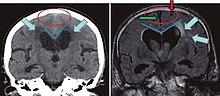

The blue arrows indicate leucoaraiosis. In the left image these may well represent transependymal CSF diapedesis due to normal pressure hydrocephalus, which in turn is suggested by the narrowed superior CSF spaces and acute callosal angle. The unilateral occurrence of these alterations in right image suggests they are probably due to vascular encephalopathy.

White matter hyperintensities can be caused by a variety of factors, including ischemia, micro-hemorrhages, gliosis, damage to small blood vessel walls, breaches of the barrier between the cerebrospinal fluid and the brain, or loss and deformation of the myelin sheath.[8] Multiple small vessel infarcts in the subcortical white matter can cause the condition, often the result of chronic hypertension leading to lipohyalinosis of the small vessels. Patients may develop subcortical dementia syndrome.[9]